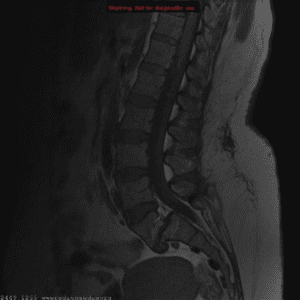

A 62-year-old woman is seen at home because her legs feel "wobbly." She has been incontinent of urine once. She has been experiencing increasing pain in her mid back over the previous fortnight. She is being treated for metastatic breast cancer with anastrozole.

There is slight weakness, rated 4/5, in hip flexion and knee extension bilaterally. Plantar reflexes are equivocal, and tendon jerks are brisk. She is tender over the 10th thoracic vertebra.

Which is the most appropriate next course of action?

The patient's symptoms and examination findings are suggestive of spinal cord compression, which is a medical emergency. Urgent imaging with an MRI of the spine is necessary to confirm the diagnosis and identify the underlying cause of the cord compression, which can include metastatic cancer, disc herniation, or spinal stenosis. Typical treatment options include surgical decompression or palliative radiation therapy. The patient may require admission to the hospital for further management.